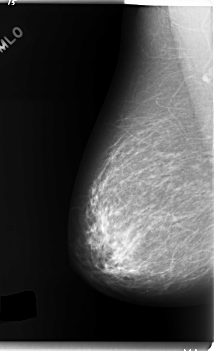

C_0124_1.RIGHT_MLO

RIGHT_MLO LINES 5952 PIXELS_PER_LINE 3624 BITS_PER_PIXEL 12 RESOLUTION 50 NON_OVERLAY